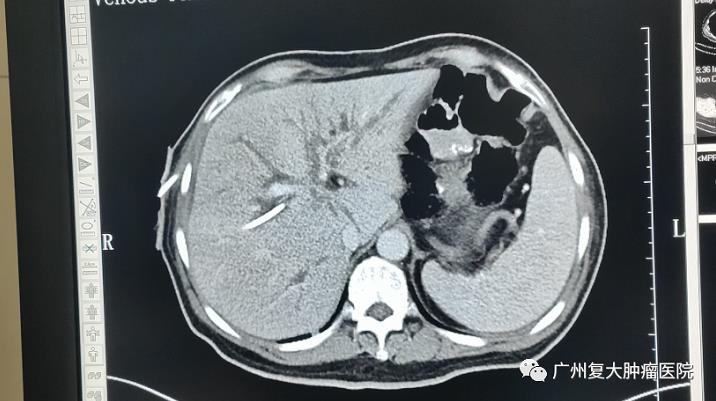

入院完善检查后发现,肝S2可见大小约2.0x1.5cm结节状低密度影,增强后静脉期肝实质隐约可见多个结节状低密度影。肝内胆管不同程度扩张,左右肝管汇合区胆管壁增厚,可见大小约1.2x0.8cm结节状软组织密度影,边界模糊,增强后可见不均匀强化。肝门部肿物活检结果显示,病变符合(肝脏)转移性腺癌,部分为印戒细胞癌,考虑为原胃癌转移。

▲入院检查